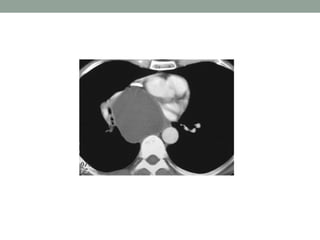

On the PA film there is a

lobulated paratracheal

stripe on the right.

On the lateral radiograph

there is a density overlying

the ascending aorta and

filling the retrosternal

space.

These findings indicate a

mass in the anterior as

well as in the middle

mediastinum.

The CT confirms the presence of lymphomas in both the

anterior and the middle mediastinum.